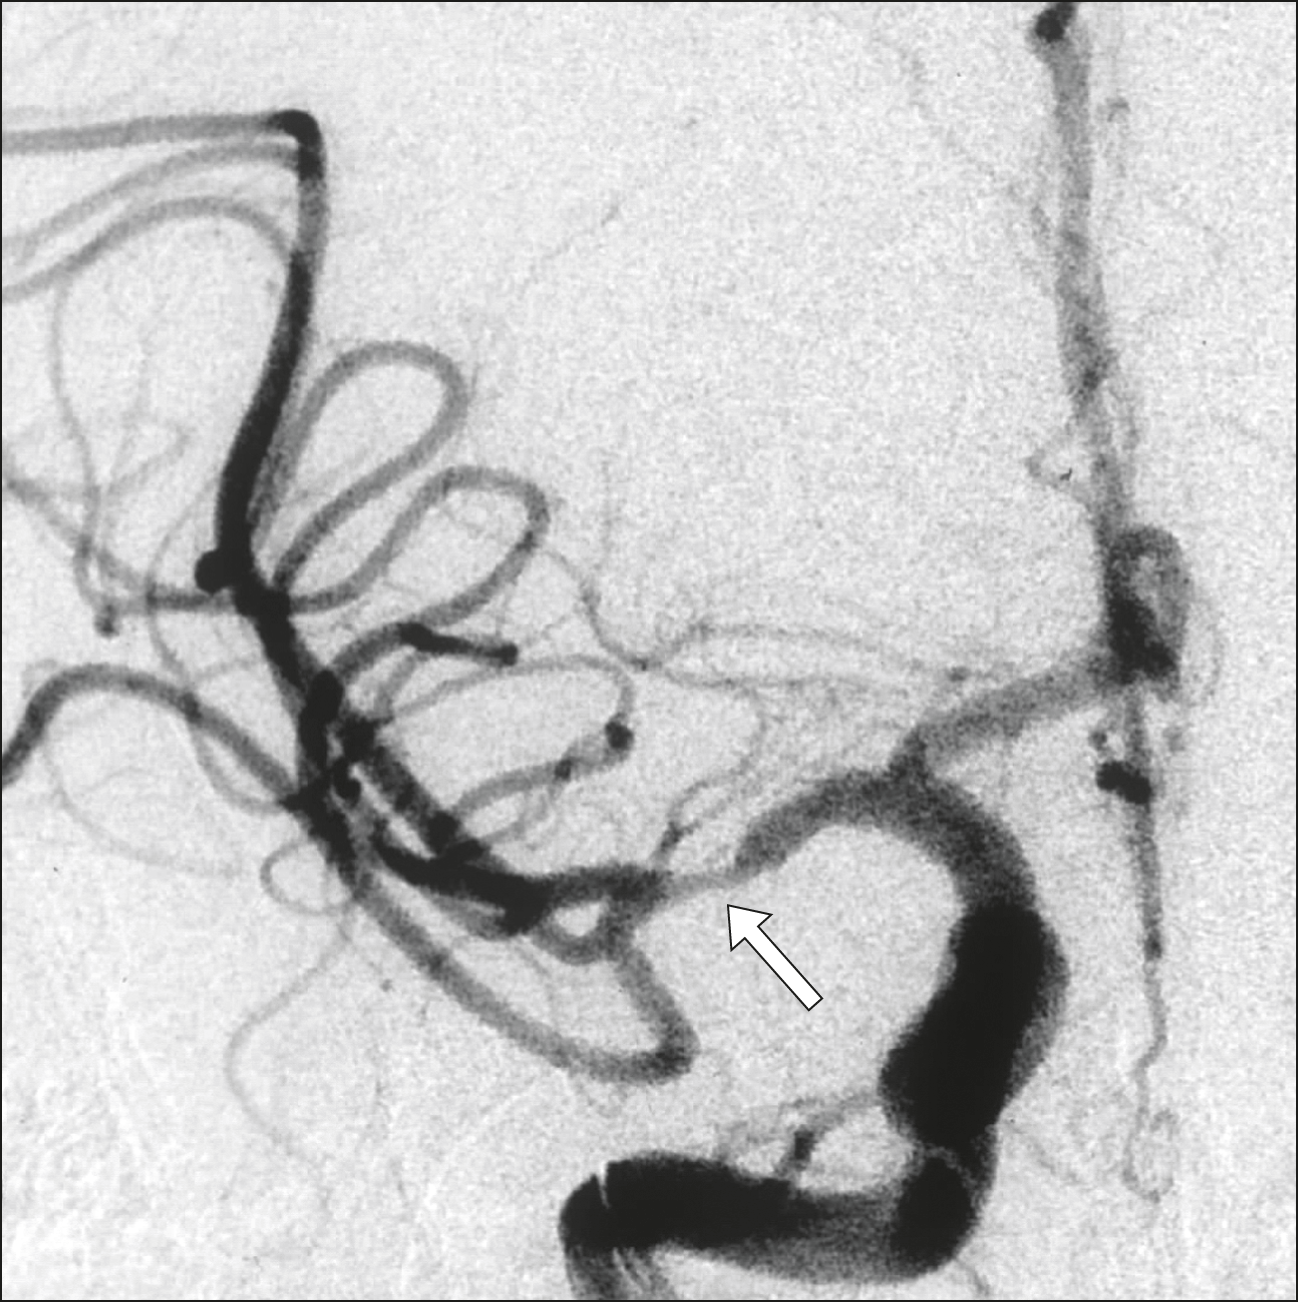

El registro nacional holandés de las intervenciones para el tratamiento inicial del ACV isquémico muestra resultados comparables a los obtenidos en los ensayos clínicos. BMJ, marzo de 2018